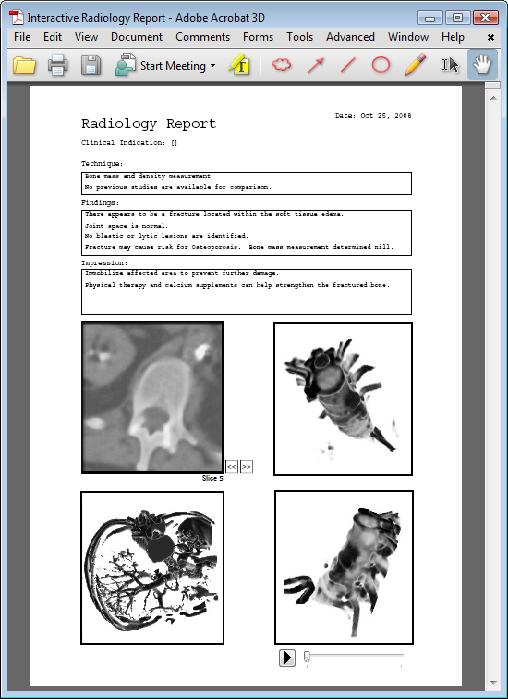

MaRRS: A Software System for Generating Multimedia Radiology Reports Using Adobe Acrobat, K. Moniz and T. McInerney, Journal of Systemics, Cybernetics and Informatics, Vol. 8, Number 3, 2010, pages 6-9.

MaRRS: A Software System for Generating Multimedia Radiology Reports Using Adobe Acrobat, K. Moniz and T. McInerney, Journal of Systemics, Cybernetics and Informatics, Vol. 8, Number 3, 2010, pages 6-9. |

MaRRS: A Software System for Generating Multimedia Radiology Reports Using Adobe Acrobat, K. Moniz and T. McInerney, The 3rd International Symposium on Bio- and Medical Informatics and Cybernetics: BMIC 2009, Orlando, FL, July 2009. Best Paper in Session Bio- and Medical Informatics and Cybernetics II, among best 10% of papers in conference and therefore selected for inclusion in Journal of Systemics, Cybernetics and Informatics |